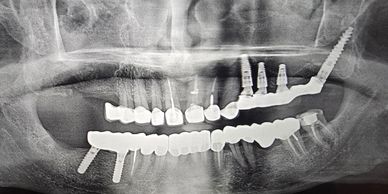

For patients with severe upper jaw bone loss, pterygoid implants anchor into the stronger pterygoid bone, providing stable support without requiring extensive bone grafting.

When traditional implant placement isn't possible due to bone deficiency, zygomatic implants utilize the cheekbone for anchorage, enabling full-arch restoration even in the most challenging cases.

Our protocols allow for immediate implant placement following tooth extraction, dramatically reducing treatment time and eliminating the need for multiple surgical appointments.